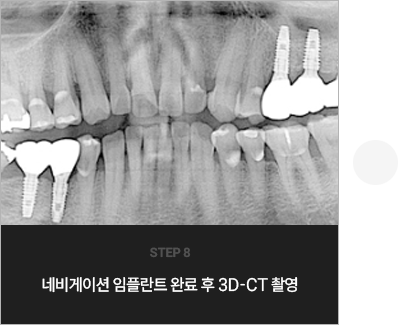

I      네비게이션 임플란트를 한 사례      I

치료 기간 : 2023.02.21 ~ 2023.11.10

* 상기 사례의 경우, 해당 의료기관에서 진료를 한 환자분의 동의를 얻어 사용되었습니다. * 치료 전후의 사진은 동일 인물과 동일한 조건에서 촬영 되었음을 알려드립니다.

* 모든 수술 및 시술은 개인에 따라 부작용고지 : 임플란트치료는 치료 후 감염, 염증,

연조직합병증, 출혈, 감각이상 등의 부작용이 있을 수 있습니다.

의료진과 충분히 상의 후 신중하게 결정하시기를 바라겠습니다.